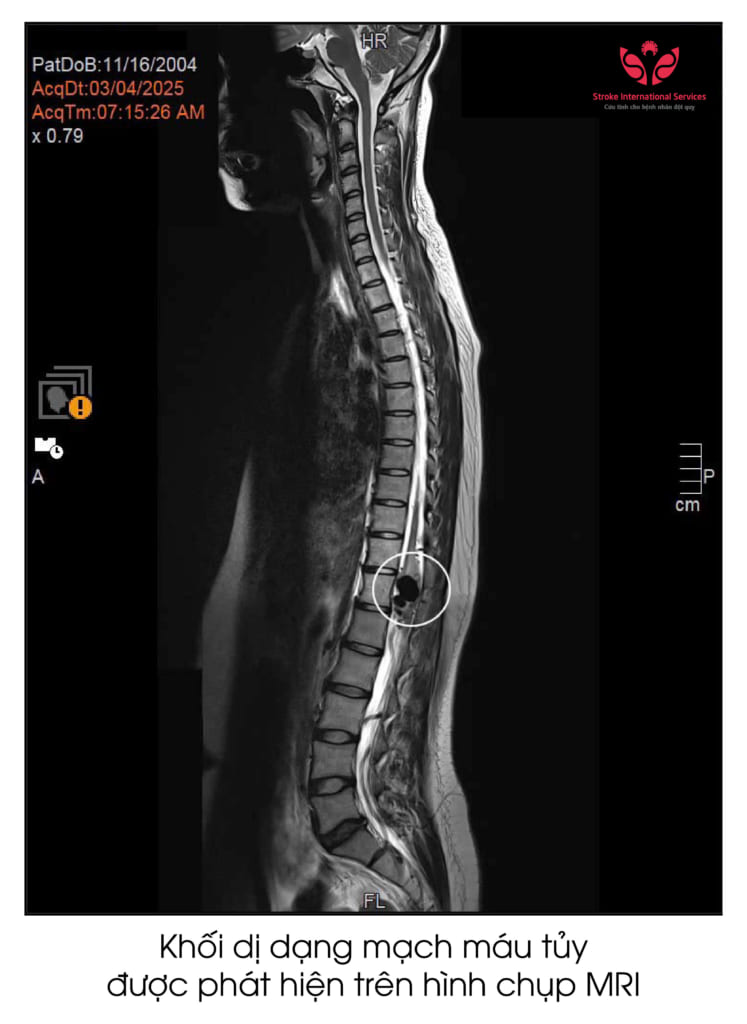

Được người quen hướng dẫn, gia đình quyết tâm đi tìm lời giải cho căn bệnh của em tại Bệnh viện ĐKQT S.I.S Cần Thơ. Tại đây, sau khi thăm khám, bác sĩ chỉ định cho em chụp MRI cột sống. Từ kết quả hình ảnh, bác sĩ chẩn đoán em mắc căn bệnh hiếm gặp dị dạng mạch máu tủy bẩm sinh. Gia đình cho biết, 19 năm qua lần đầu tiên em được chụp MRI cột sống và tìm ra bệnh.

“Khi bệnh nhân đến khám, từ các triệu chứng điển hình các bác sĩ nghi ngờ có dấu hiệu tổn thương hệ thần kinh tủy sống và chỉ định cho bệnh nhân chụp cộng hưởng từ cột sống. Kết quả hình ảnh học cho thấy khối dị dạng lớn ở vùng mạch máu tủy. Khối dị dạng này gây phù tủy, chèn ép rất nặng gây yếu chân. Thông thường đường kính tủy sống khoảng 2 cm. Nhưng túi phình dị dạng có đường kính lên đến 2,4 cm đã chèn ép toàn bộ vùng chóp cùng tủy trong đó có chùm đuôi ngựa.

TS.BS Trần Chí Cường lưu ý thêm: “Từ trường hợp của em Tiêu Hồng Như, mặc dù tỷ lệ dị dạng mạch máu tủy sống, dị dạng mạch máu tủy cổ rất hiếm gặp nhưng vẫn không nên bỏ qua. Xin quý đồng nghiệp lưu ý nếu như chụp X-quang hay khám lâm sàng thông thường thì khó có thể chẩn đoán dị dạng mạch máu tủy. Hiện tại, phương pháp cận lâm sàng tốt nhất để chẩn đoán đó là chụp cộng hưởng từ. Minh chứng đó là qua hình ảnh chụp cộng hưởng từ bằng máy MRI 3.0 Tesla tại Bệnh viện ĐKQT S.I.S Cần Thơ có thể thấy rõ toàn bộ cột sống cũng như khối dị dạng mà không cần phải tiêm bất kỳ loại thuốc tương phản nào”.